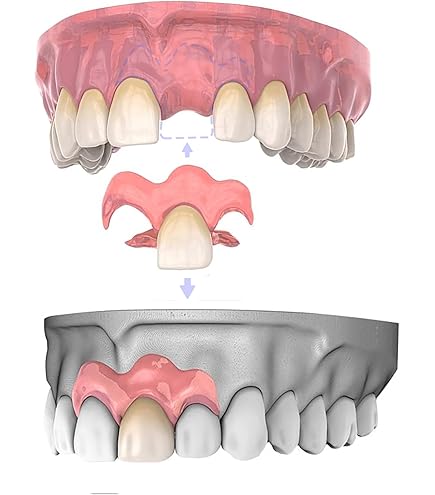

Make the Dental mamelon! こだわりの前歯部精密修復| 歯科総合。Amazon.co.jp: Make the Dental mamelon!―こだわりの前歯部精密。Amazon.co.jp: Make the Dental mamelon!―こだわりの前歯部精密。「Make the Dental mamelon!―こだわりの前歯部精密修復」菅原佳広定価: ¥ 9350(税込)⚠️裁断済です。Make the Dental mamelon! の購入ならWHITE CROSS。⚠️背表紙を切断して1ページずつバラバラにしたものですので、普通の本のように読むことはできません。「チベット仏教の神髄」 チベットハウス編 小林秀英訳。裁断済の意味が理解できない方のご購入はご遠慮ください。立命館大学2017〜2025まで5冊。裁断済みであるため全体的に状態が悪いとしていますが、書き込みやマーカーなどはなく裁断済みであること以外は状態は良いと思います。かいじゅうずかん 初版。神経質な方のご購入はご遠慮ください。KING OF BASIC メンズカットのすべて。本 \rBOOK \r医学\r保存修復\r保存修復学\rエンド\rペリオ\r国試対策\r義歯\r総義歯\r部分床義歯\r全部床義歯\rフルデンチャー\rパーシャルデンチャー\rDVD\r外科\r歯周外科\rCR\rコンポジットレジン\rSRP\r歯科医師\r歯科衛生士\r歯科技工士\r基礎\r基本\r矯正ダイレクトボンディング#菅原佳広 #本 #自然/医療・薬学・健康